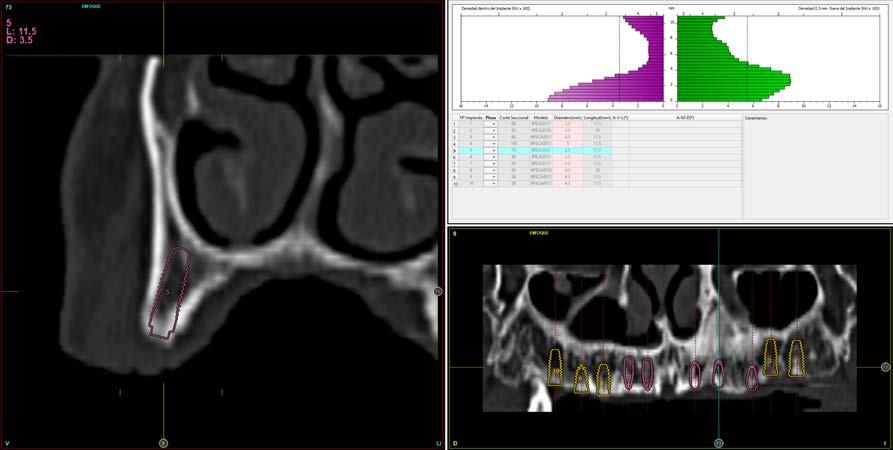

Figura 2. Corte seccional de la zona anterior del maxilar que muestra la planificación de los implantes a insertar.

En los cortes del cone-beam de planificación se observa la posibilidad de colocar implantes estrechos en la zona anterior del maxilar, así como implantes de mayor diámetro y longitud en los sectores posteriores (Figura 2).